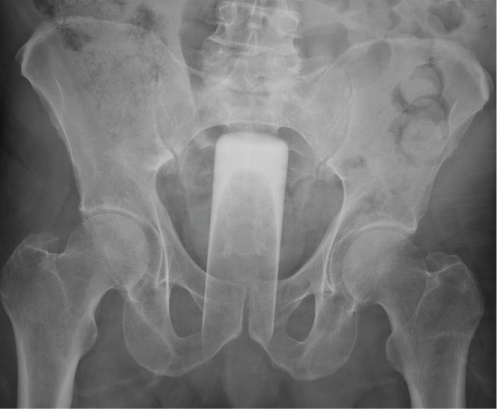

A 62-year-old man with no significant past medical history presented to the emergency department about one hour after insertion of a tall thin glass into his rectum. The patient attempted to remove the glass but the end of it broke off. With the onset of rectal pain and bleeding, he decided to go to the ER via EMS. The patient had normal vital signs on presentation. Digital rectal exam was not performed due to the presence of broken glass. External perianal exam was significant for blood at the anal verge. X-ray confirmed presence of the retained foreign body (Figure 1). The patient brought a matching glass, so that we could understand what the foreign body looked like (Figure 2). Due to the presence of rectal bleeding, we knew that there was high likelihood of rectal injury. The patient was brought to the operating room for anorectal exam under anesthesia with removal of the foreign body. He was placed in high lithotomy position in the candy cane stirrups. A Lone Star retractor was carefully placed to evert the anus. Fractured glass was visible in the anus pushing into the anal sphincter. The glass was thin and was pushing up against the wall of the anus/distal rectum circumferentially. A few pieces of glass broke off while attempting to place retractors around the foreign body. Ultimately the only retractor that we were able to successfully place between the glass and the rectum was a narrow malleable. Numerous malleable retractors were placed circumferentially around the foreign body to protect the anal canal from the sharp, jagged edge of the glass cup. We attempted to remove the glass with this technique; however the closed end of the glass was suctioned to the rectal wall proximally. We passed an Argyle suction catheter with a chimney valve past the glass into the rectal lumen and insufflated air above the glass which successfully released the suction. With this maneuver, we were able to shimmy the glass out using the circumferential malleable retractors. The glass measured 16 cm in length by 5 cm in width (Figure 3). There was 200 cc of blood in the rectum after the glass was removed. Transanal endoscopic microsurgery (TEMS) was performed to assess for rectal injury. A very patulous anus precluded the use of flexible sigmoidoscopy due to inadequate insufflation. TEMS revealed two 1 cm mucosal injuries in the distal third of the rectum which appeared superficial and required no intervention. There was a 2-3 centimeter left posterior quadrant anal sphincter injury involving the internal anal sphincter and a few fibers of the external anal sphincter. This was repaired with a running 2-0 Vicryl suture and the distal aspect was left open to allow for drainage. There was also an anal mucosal injury over a large hemorrhoid which was repaired with a Vicryl suture. Given that there was no frank full-thickness rectal injury, we elected not to perform a diverting stoma. Post-operatively, the patient did well. A CT scan of the pelvis was performed to evaluate for any glass fragments not previously identified during examination under anesthesia. This was negative for retained foreign body. The patient tolerated a diet and was discharged on post-operative day 0.

Figure 1: X-ray confirmed presence of the retained foreign body. View Figure 1